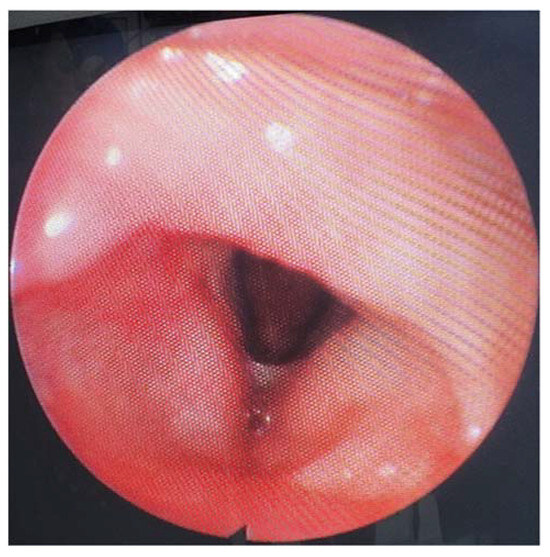

A postcontrast computer-tomography (CT) scan of the neck revealed an expanding tumor, which was intensely enhancing and heterogenous, with dimensions of 28/24 mm in diameter. It had mainly developed inside the hypopharynx and larynx and centered itself at the left pyriform sinus that deviates the epiglottis, embedding itself in the left aryepiglottic fold, the arytenoid cartilage, and the false vocal fold, and bulging into the laryngeal inlet, thereby coming into close contact with the right arytenoid cartilage. At the upper pole, it extended from the greater horn of the hyoid bone along the entire length of the thyroid cartilage, down to a line that passed across the level as that of the arytenoid cartilage. The CT scan bilaterally objectified the presence of some enlarged cervical lymph nodes in group III (Figure 2).

Figure 2.

Enhanced CT scan of the tumor (marked by star).